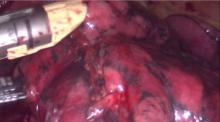

A 3-4 cm utility incision was performed anteriorly in the 5th intercostal space, while the thoracoscopic access was performed in the 8th intercostal space in the posterior axillary line. A 4 cm mass was detected in the right lower lobe, too deep and central for wedge resection. The superior segment was not affected. A basilar segmentectomy was completed. A single chest tube was inserted through the thoracoscopic access at the end of the procedure. It was removed the day after, and the patient was discharged on the second postoperative day.